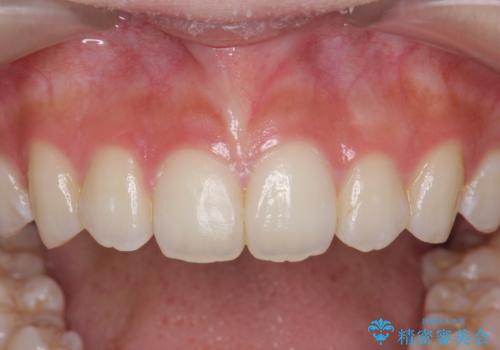

インビザラインライトで行う短期マウスピース矯正治療

- 前歯のガタつきを並べたいたいと、矯正治療を希望され来院されました。

とにかく短期間で前歯だけの治療を行いという希望が強く、全体矯正と前歯だけの部分矯正の仕上がりのイメージを確認したのち14枚のマウスピースで前歯のみの矯正治療を行っていくこととしました。

インビザラインライトは軽度なガタつきや傾斜の改善に用いられる全14枚のマウスピース矯正です。

短期間で治療の終了が見込めるだけでなく、料金もインビザラインフルに比べリーズナブルです。